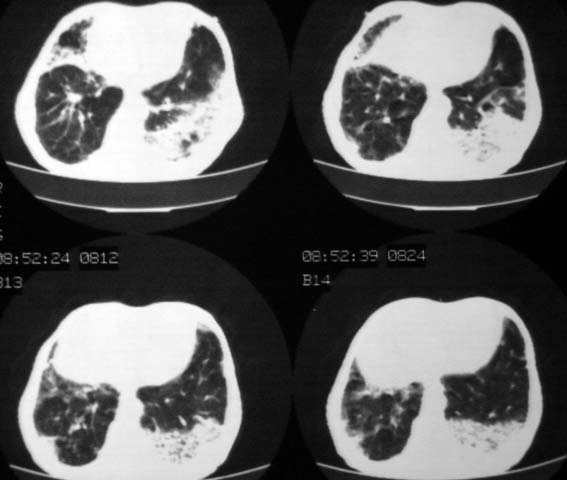

男,85岁,发热2月, 血常规:hgb99g/l.rbc2.55×1012/l.wbc3.8×109/l.n78.2%  l20.7% m1.1%.  hct26.3% .血沉20mm/hg.痰检结核杆菌阴性。ddp阳性。痰少粘稠色白。无咳血。

1.右上肺陈旧性肺结核灶;

2.左上肺、双下肺及右中叶肺炎(左上肺肺炎治疗后好转)

右上肺陈旧性肺结核灶,双肺感染灶〔大部份纤维化〕,肺气肿.

双肺继发型肺结核,肺纤维化,肺气肿,胸膜肥厚黏连。